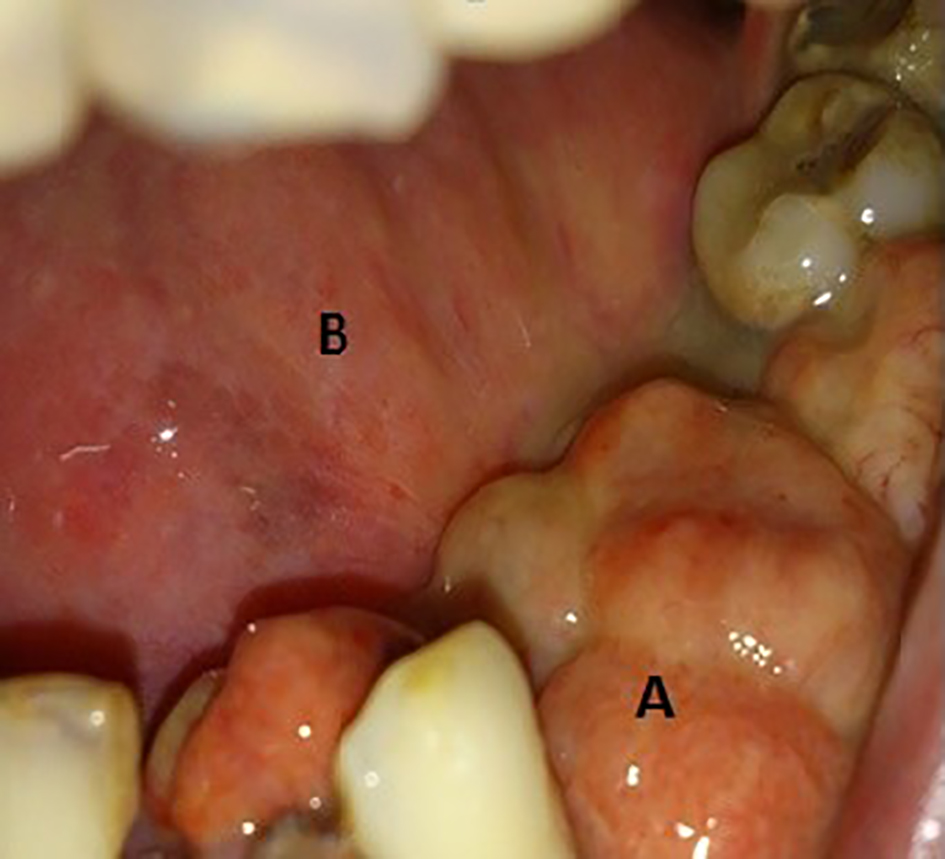

Patient was quite well and disease free for 4 years until 2013, when he noticed a pea-sized tender swelling on inner aspect of the left lower alveolus. The lesion was excised and biopsy showed polyploid pyogenic granuloma with no signs of malignancy. The swelling recurred within 4 months. Patient complained of progressive and painful enlargement of the lesion, loosening of teeth and decreased mouth opening. During intra-oral examination, three exophytic growths with smooth erythematous surface were found on left mandibular quadrant with the largest measuring about 3 × 2 cm, attached firmly on the alveolar bone with loss of canine and first and second premolars (Fig. 2). The smaller lesions measuring 1.5 × 1.5 and 1 × 1 cm were found on medial and posterior aspects, respectively. No extra-oral abnormality was observed and cervical lymph nodes were non-palpable. Incisional biopsy revealed spindle cell carcinoma. Complete surgical excision was planned. After all aseptic measures, patient lied in a supine position, intubated and anesthetized. Left-sided segmental mandibulectomy was performed through visor’s incision (transcervical approach). En block tumor resection was undertaken. Incision was extended caudally to approach level I, II and III lymph nodes. Bilateral supra-omohyoid neck dissection was performed. Titanium reconstruction plate was applied over the defect, followed by repair of the floor of the mouth. Neck incision was closed and drains were placed.

![]() Click for large image | Figure 2. (A) A 3 × 2 cm growth at left mandibular quadrant with loss of canine, first and second premolars. (B) Site of previous hemi-glossectomy. |